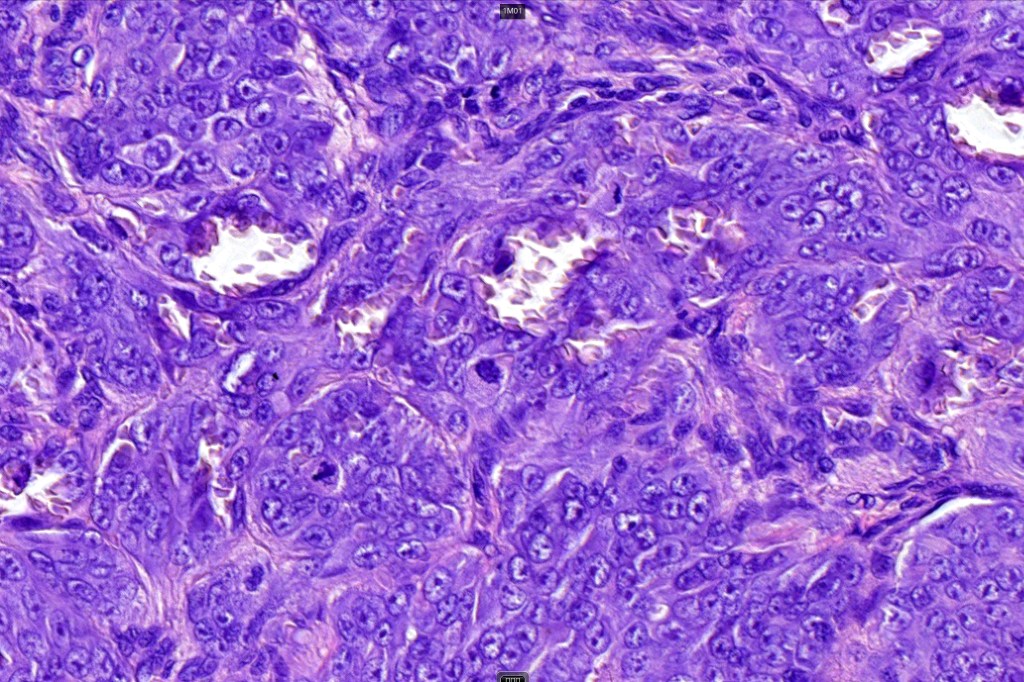

Histological features

•Large nodules which often show impaired maturation

•Loss of gradient with HMB45 and Ki67

•>20% Ki67 expression

•TERT promoter & PTEN mutations

•DNA copy-number variations